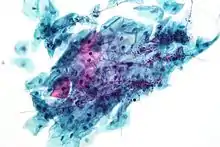

Micrograph of a Pap test showing a low-grade intraepithelial lesion (LSIL) and benign endocervical mucosa. Pap stain.

Pap tests commonly examine epithelial abnormalities, such as metaplasia, dysplasia, or borderline changes, all of which may be indicative of CIN. Nuclei will stain dark blue, squamous cells will stain green and keratinised cells will stain pink/ orange. Koilocytes may be observed where there is some dyskaryosis (of epithelium). The nucleus in koilocytes is typically irregular, indicating possible cause for concern; requiring further confirmatory screens and tests.